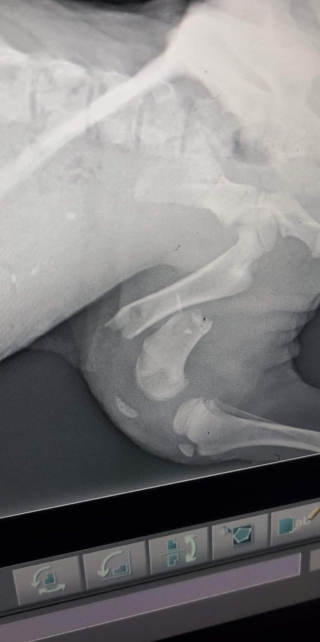

Pour Rita, le diagnostic s'allongeait davantage. La pauvre avait plusieurs fractures dans le bas du corps, plus précisément au niveau du bassin et des membres inférieurs. Il n’y avait nul autre choix que de l’opérer.

Finalement, Rita a pu se rendre au bloc opératoire. Les vétérinaires ont constaté qu’une bactérie avait fait son nid sur l'un de ses os, et qu’elle devait rester sous antibiotique pour éviter les complications. Mais de manière générale, elle était tirée d’affaire.